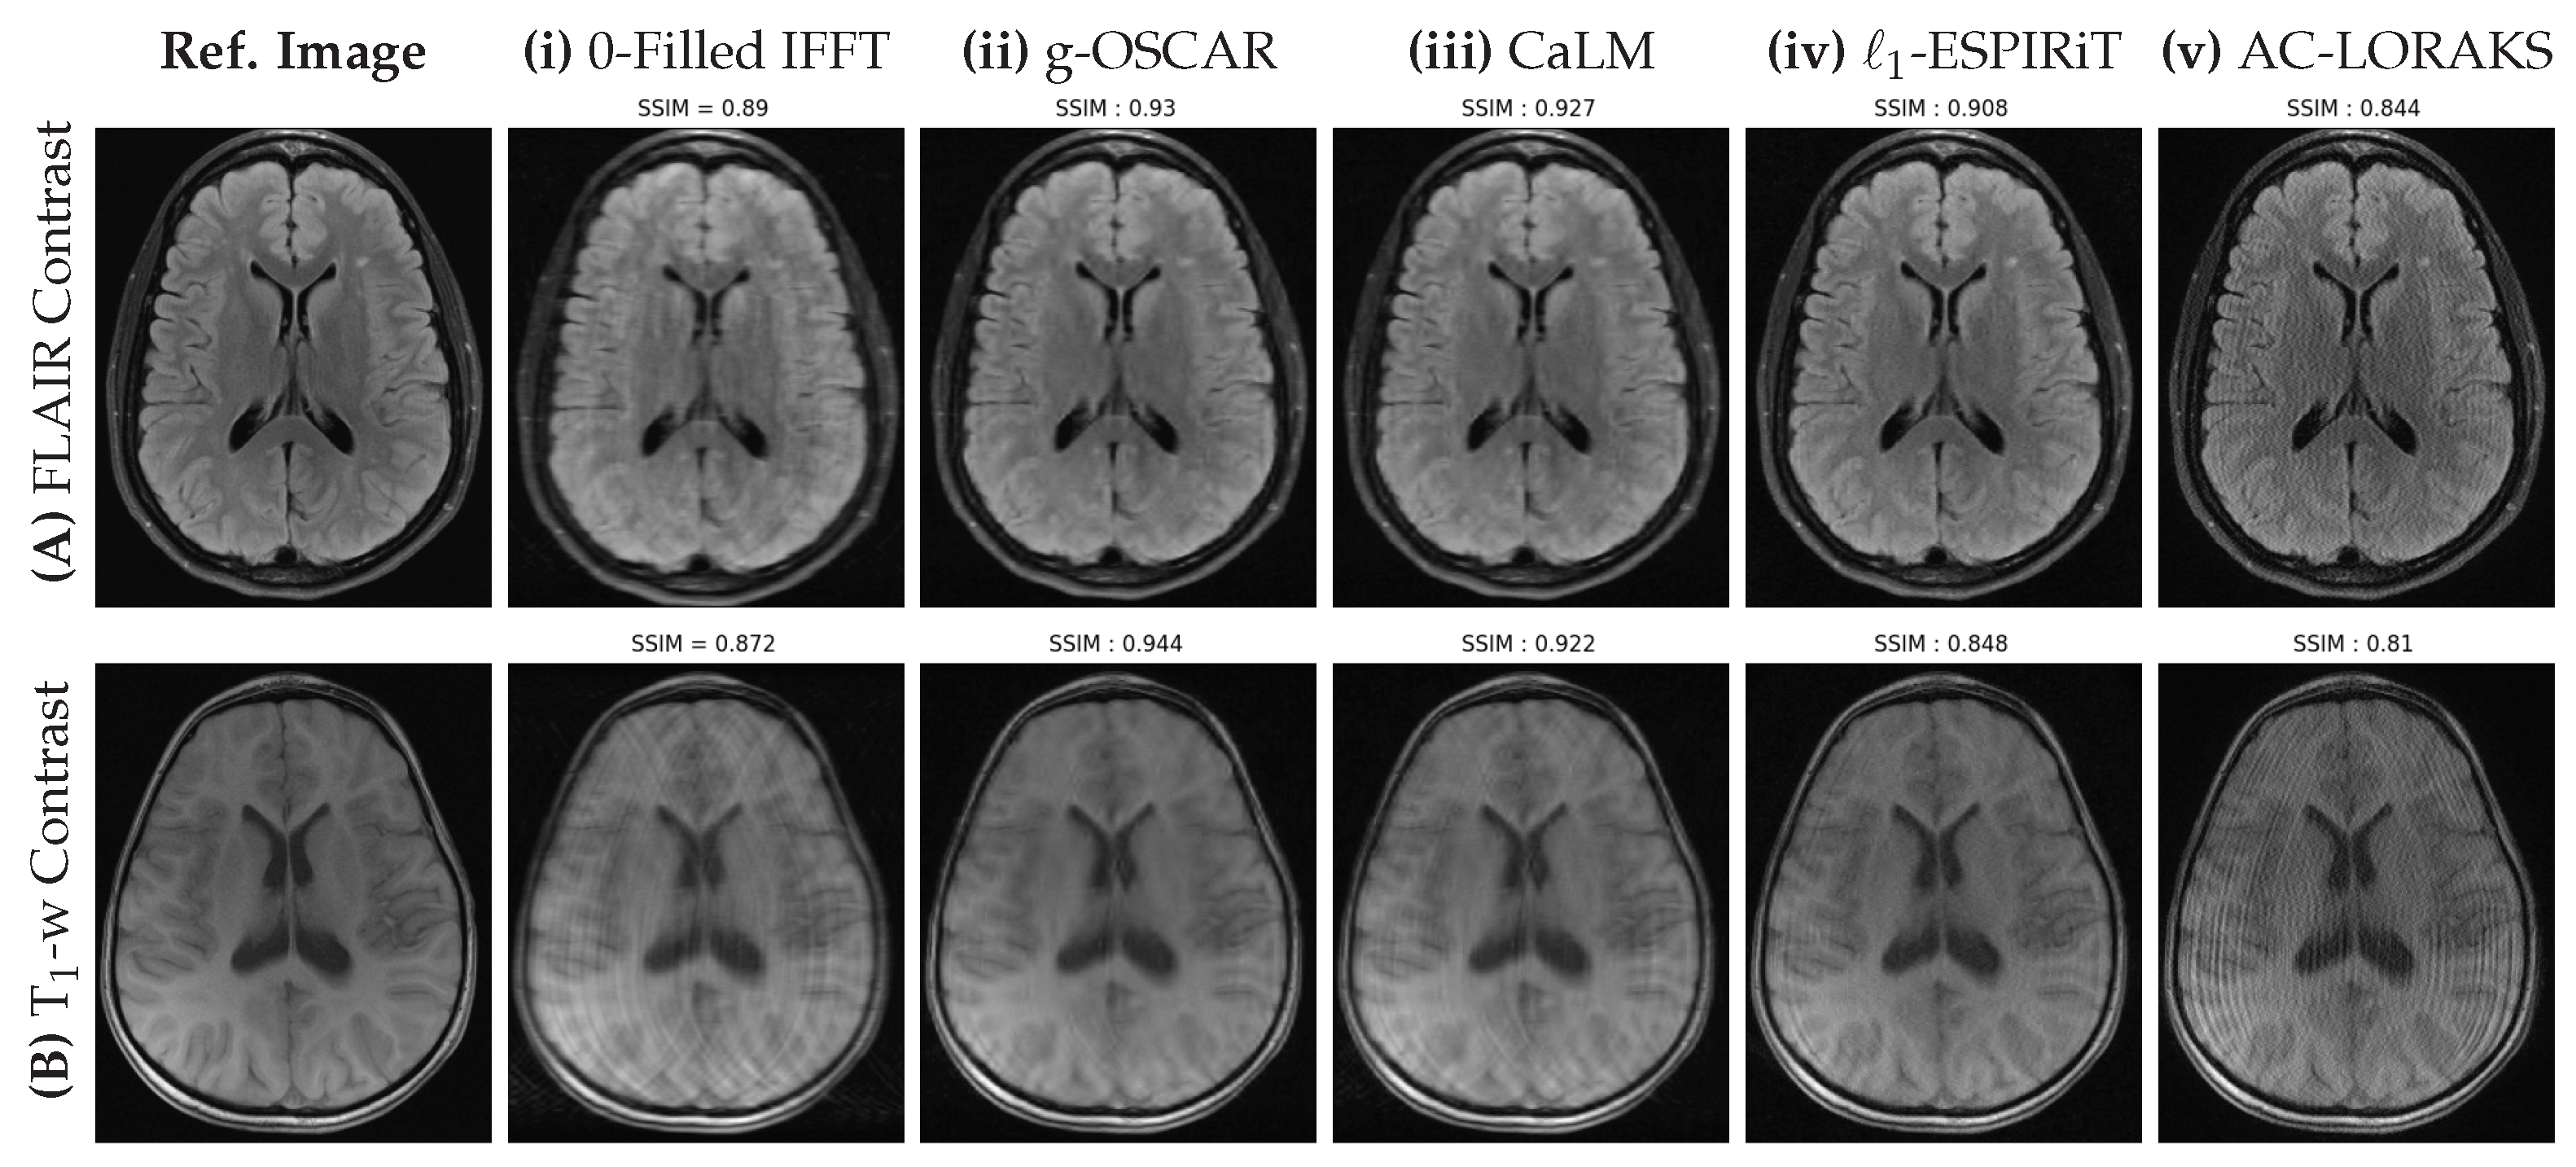

5.1. Retrospective Studies